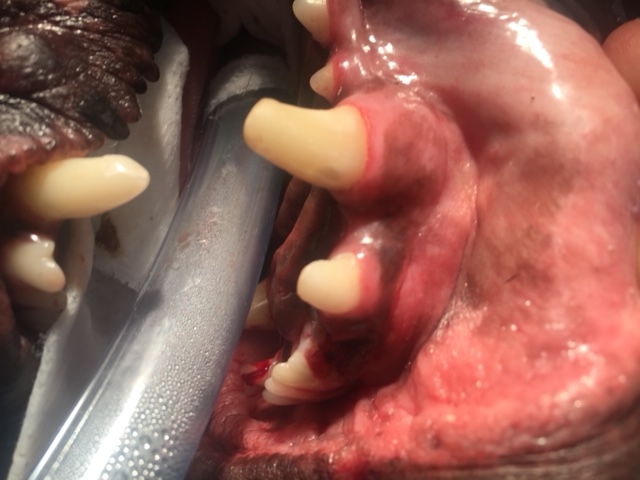

As you can see in the photos the canine tooth is massive. The crown, which is the part that extends into the mouth, is only a small part of this tooth. The root is large and held in the jaw by very a strong periodontal ligament that has fibres running from the tooth to the surrounding bone.

Structurally canine teeth are important as they hold the shape of the mouth, provide structure to the jaw, keep the tongue in place in the mouth (mandibular/lower canines) and are used in eating, holding and playing. If a canine tooth is fractured and the pulp is exposed, then the two options for a pet over 1 year old are a root canal or extraction. Under 1 year old the apex of the tooth may not be closed so a root canal may not be able to be done.

For an extraction, a large gingival flap is made and alevolar bone is burred away. The amount of bone burred away will be less if a vet-tome instrument is used. The tooth is then elevated and luxated out of the socket. When teeth are fractured (as opposed to periodontally diseased), the tooth is normally structurally sound so extraction of the tooth does require a fair amount of force. It is relatively traumatic. Post extraction the socket is flushed with saline and the gingival flap sutured closed. It is important the dog eats soft food and does not chew on anything hard while the gum is healing as wound breakdown can occur and the dog animal may need another anesthetic for resuturing the gingival flap.